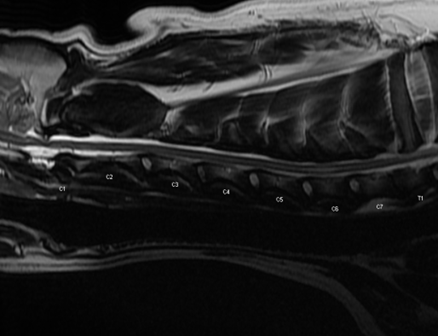

In the sagittal T2-weighted image below, there is a central hyperintensity within the spinal cord centered over C6. This lesion was isointense on T1w and did not contrast-enhance.